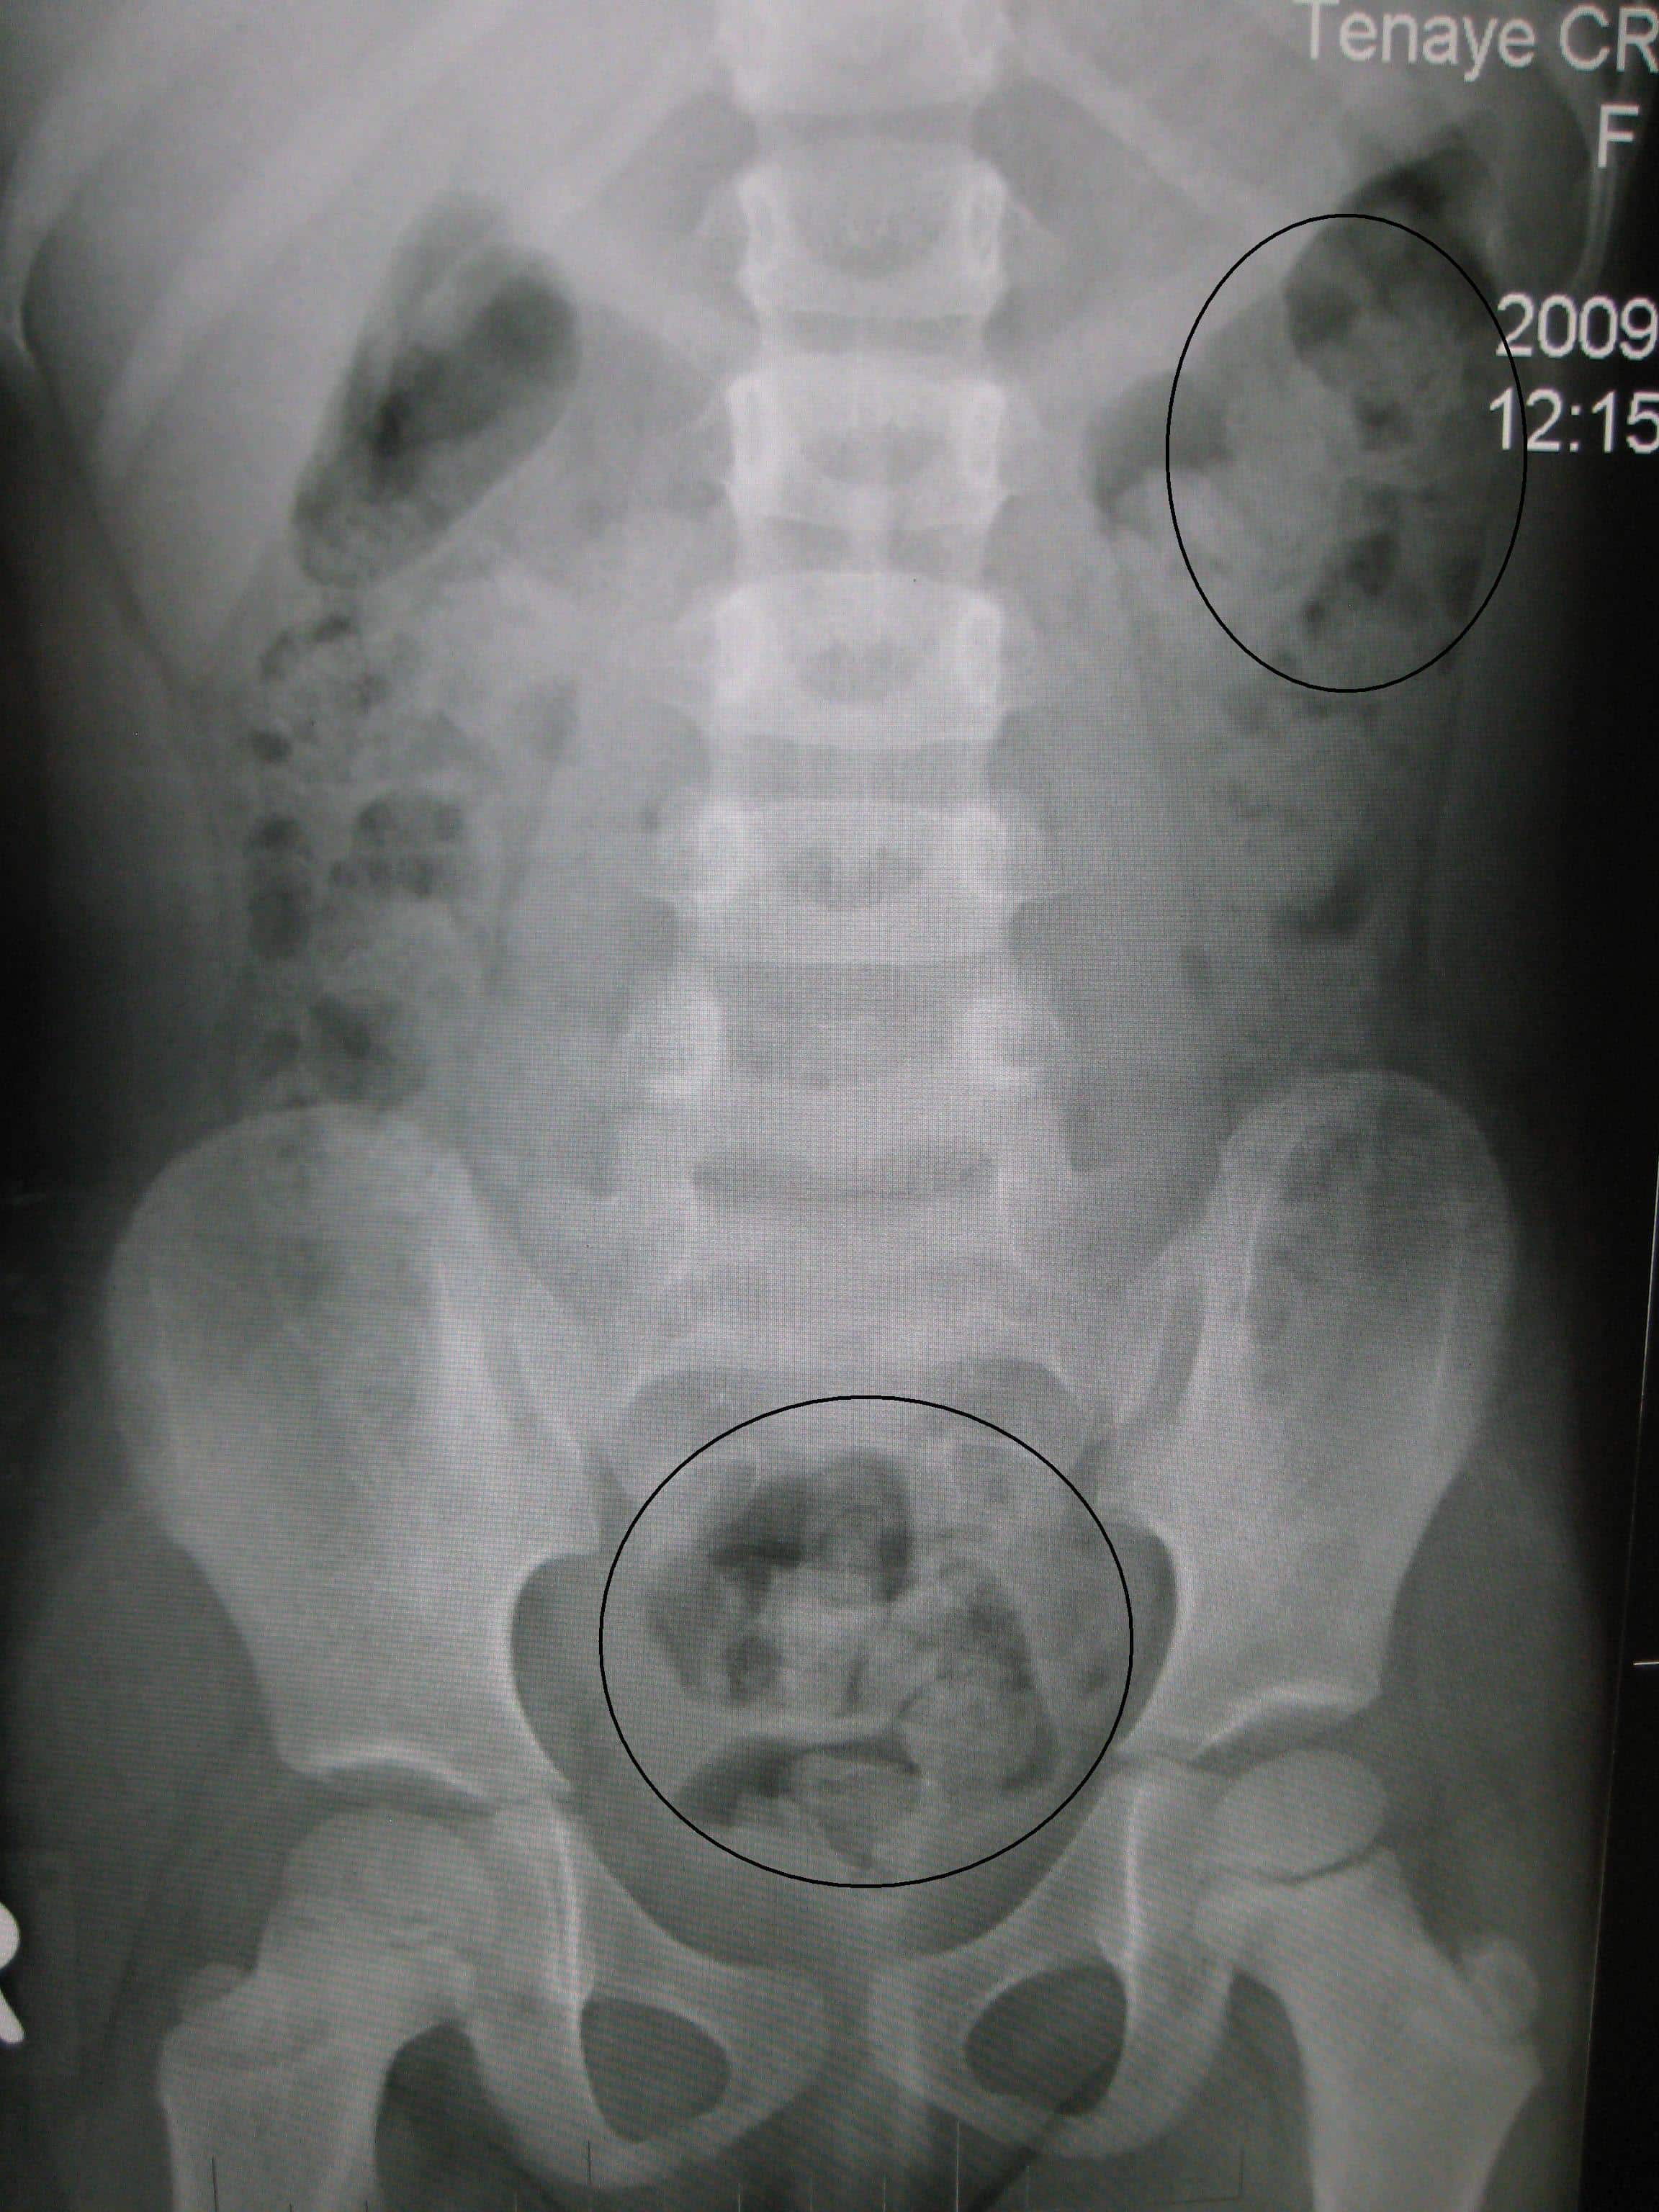

Some causes of abdominal pain apply mainly to children, such as colic, intussusception, and testicular torsion. Web even stool that is not hard may be difficult to pass. Web abdominal pain commonly presents with constipation, which occurs when you have difficulty or cannot have a bowel movement.

The need to use a finger to pass stool. Sometimes, though, lower abdominal pain can be a symptom of a more serious issue. Web causes diagnosis treatment lower abdominal pain has a lot of causes and can feel significantly different depending on the cause.

Web Causes When To See A Doctor Treatment Summary Abdominal Cramps And Pain Often Occur Alongside Constipation.

Fewer than three stools a week. Possible causes range from dietary choices and lack of exercise to medical. There are many causes of abdominal pain.